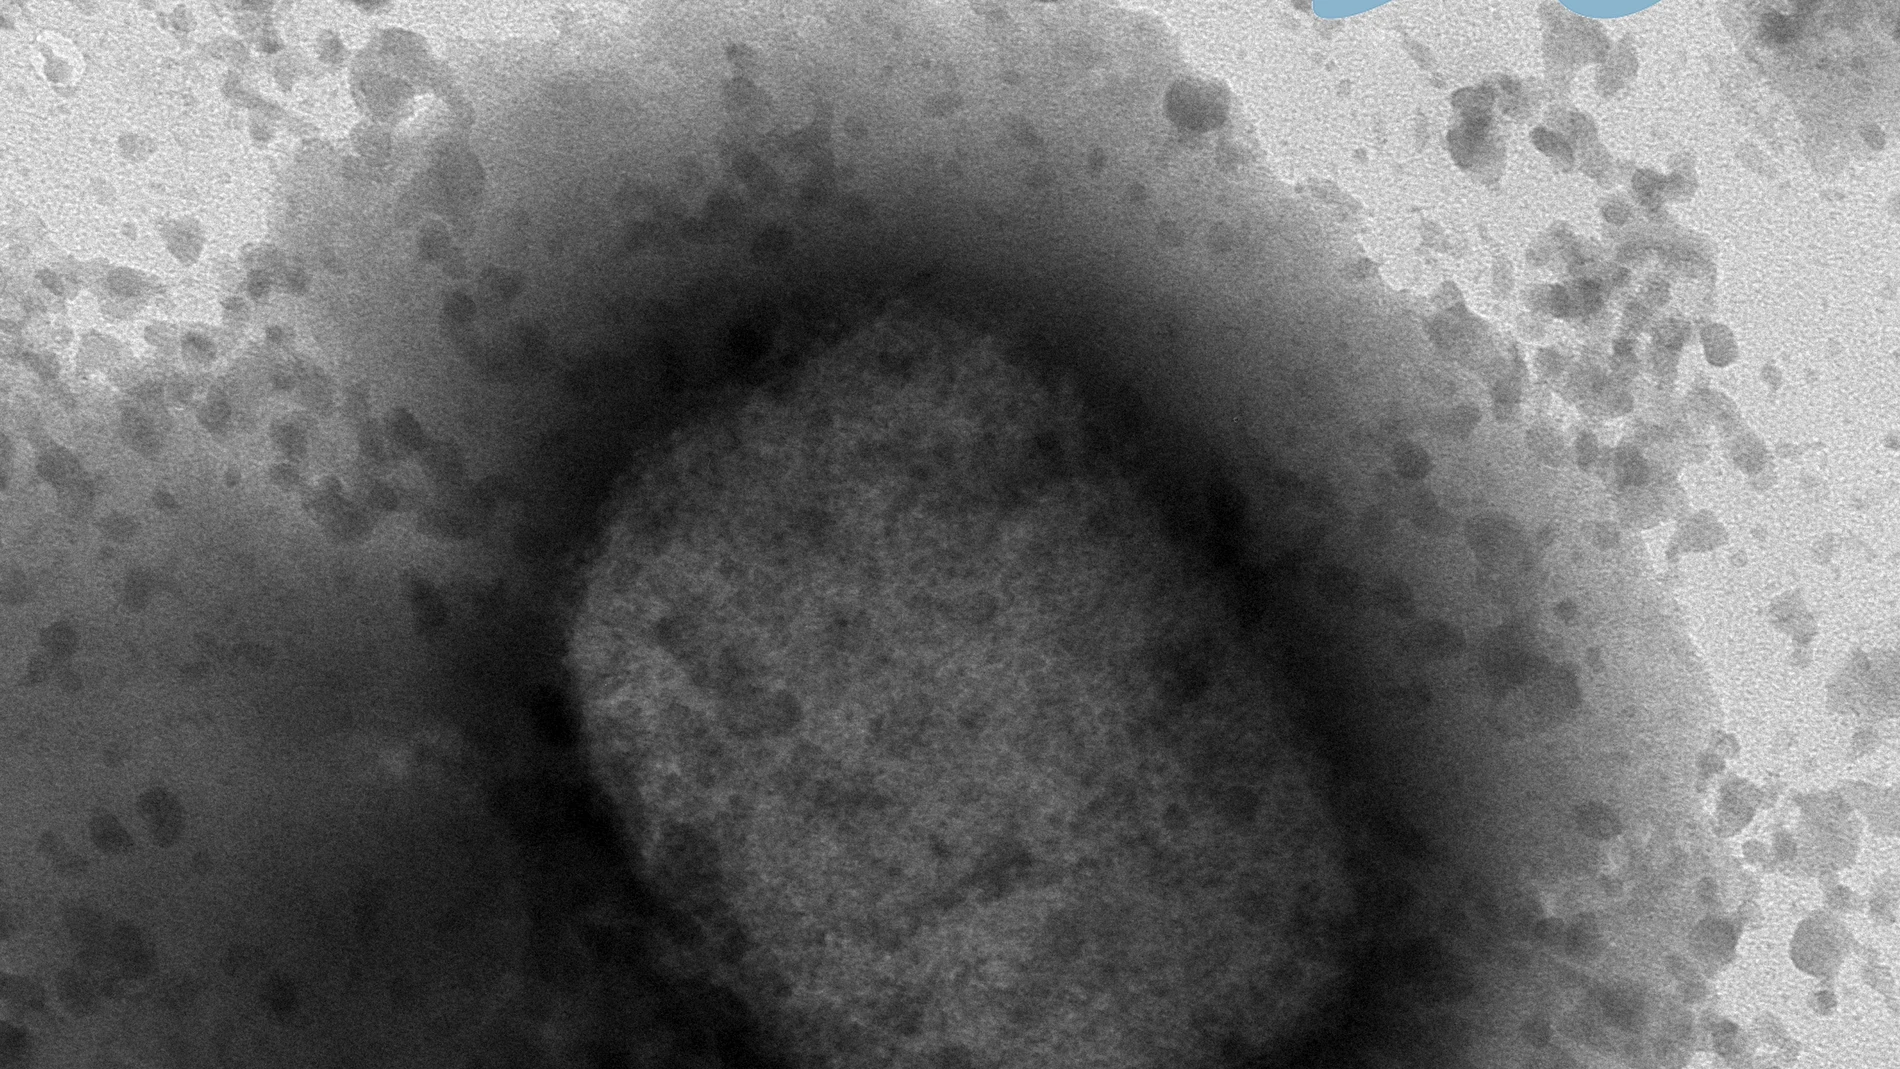

Buenas noticias en Castilla y León. Y es que el Centro Nacional de Microbiología de Majadahonda (Madrid) ha informado esta tarde a la Dirección General de Salud Pública de la Junta de Castilla y León que la PCR correspondiente al caso sospechoso de viruela del mono en la Comunidad, comunicado ayer al Centro Coordinador de Alertas y Emergencias Sanitarias, ha dado resultado negativo, por lo que ha quedado descartado como caso de esta enfermedad.